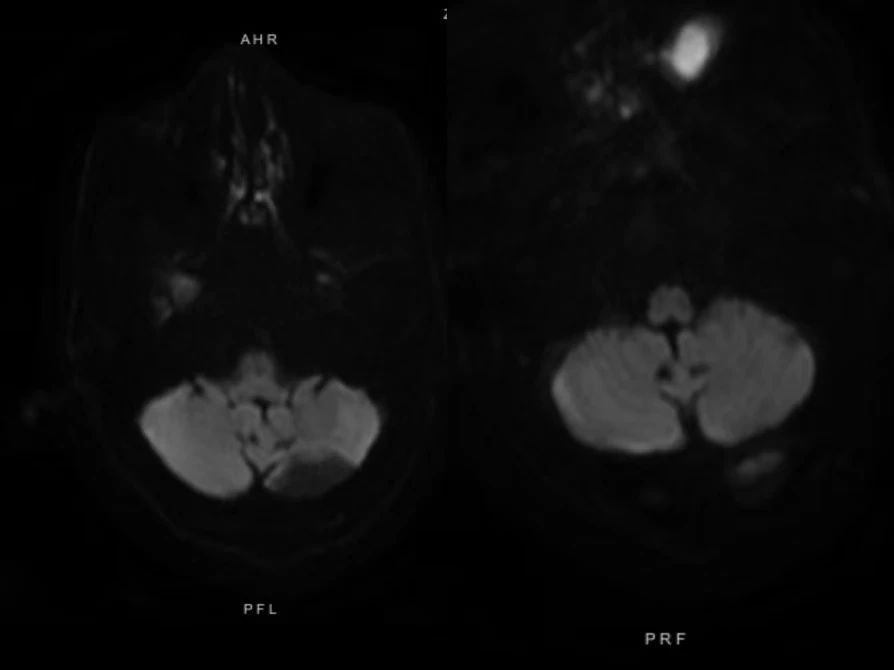

头颅磁共振弥散加权成像即头颅DWI,是功能磁共振的一种,可用于缺血性脑血管病的早期诊断,DWI扫描序列能发现磁共振其他序列无法检出的病灶,还能够对有些病变的鉴别诊断起到决定性的作用。DWI扫描序列在临床中的应用,主要体现在以下几个方面:

四是对表皮样囊肿、脑脓肿等病变具有定性诊断的意义。

总之,DWI是磁共振临床应用中的一个非常重要的序列,当我们需要发现新发脑梗塞时,就进行DWI扫描;当我们检查脑外伤患者时,需要进行DWI扫描;当我们需要鉴别病变的良恶性时、对表皮样囊肿、脑脓肿等疾病定性诊断时,我们要进行DWI 扫描。